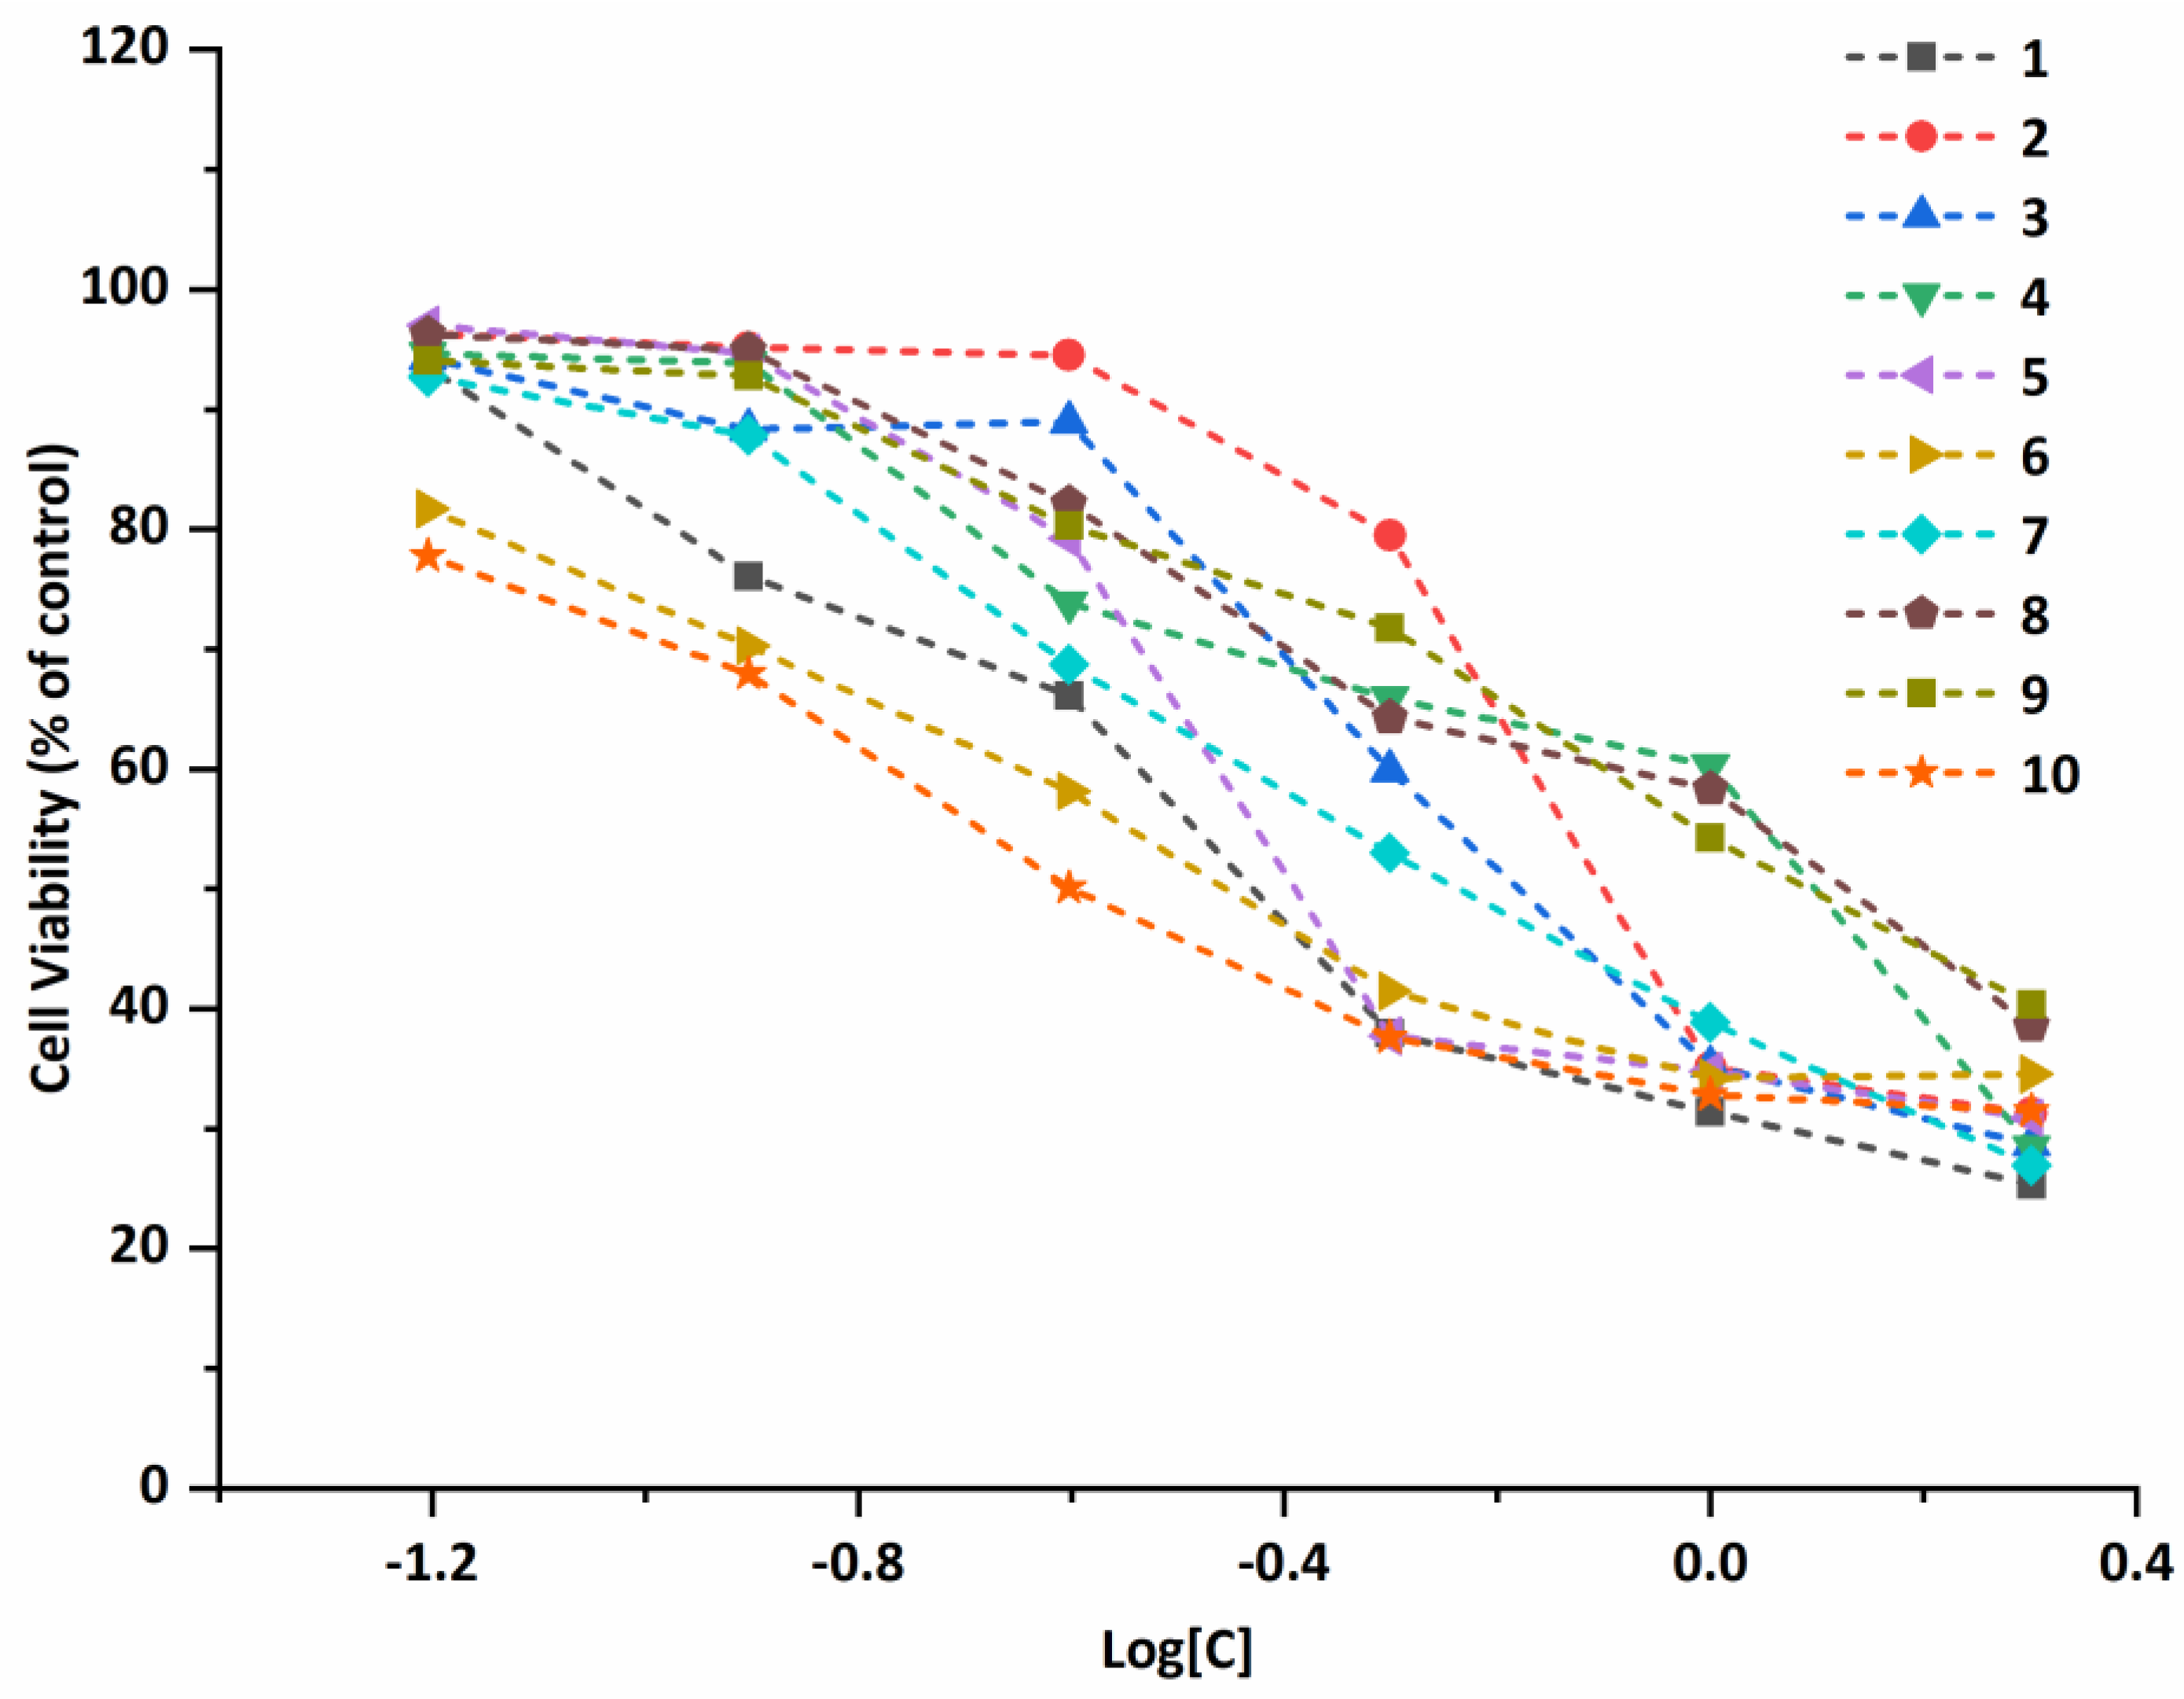

2.5. Antiproliferative Properties

3.6. Antiproliferative Activity In Vitro

| Compound | A549 | Bel-7402 | MCF-7 | Eca-109 | ||||

|---|---|---|---|---|---|---|---|---|

| IC50 (μM) | 95% Confidence Intervals (μM) | IC50 (μM) | 95% Confidence Intervals (μM) | IC50 (μM) | 95% Confidence Intervals (μM) | IC50 (μM) | 95% Confidence Intervals (μM) | |

| 1 | 0.440 | 0.384–0.504 | 1.309 | 1.098–1.560 | 1.486 | 0.855–2.582 | 1.251 | 1.024–1.528 |

| 2 | 0.933 | 0.821–1.061 | 1.842 | 1.741–1.949 | 2.769 | 1.584–4.840 | 2.017 | 1.507–2.701 |

| 3 | 0.756 | 0.672–0.852 | 1.470 | 1.202–1.797 | 1.358 | 0.911–2.025 | 1.821 | 1.475–2.247 |

| 4 | 1.042 | 0.858–1.265 | 1.883 | 1.691–2.096 | 0.589 | 0.336–1.035 | 3.320 | 2.996–3.680 |

| 5 | 0.586 | 0.476–0.722 | 1.435 | 1.150–1.790 | 1.187 | 0.655–2.152 | 1.722 | 1.360–2.181 |

| 6 | 0.435 | 0.370–0.513 | 0.660 | 0.447–0.975 | 1.956 | 1.148–3.332 | 1.198 | 0.908–1.580 |

| 7 | 0.633 | 0.568–0.705 | 1.636 | 1.459–1.835 | 0.374 | 0.229–0.609 | 1.045 | 0.862–1.266 |

| 8 | 1.228 | 0.938–1.608 | 1.557 | 1.396–1.736 | 2.428 | 1.870–3.153 | 1.215 | 0.852–1.732 |

| 9 | 1.270 | 1.165–1.385 | 1.804 | 1.521–2.139 | 3.548 | 3.016–4.173 | 1.280 | 0.985–1.665 |

| 10 | 0.333 | 0.279–0.396 | 0.730 | 0.604–0.883 | 1.764 | 0.999–3.116 | 1.193 | 0.841–1.692 |

| Cisplatin | 5.082 | 4.639–5.568 | 3.088 | 2.856–3.340 | 11.49 | 9.435–14.00 | 11.99 | 10.79–13.32 |